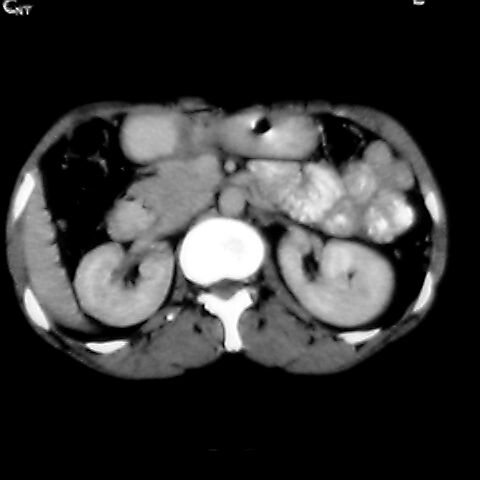

女 48岁 食道癌术前体检发现脾占位。

1肝右下叶小囊肿2右肾上极囊肿或错构瘤3脾脏不典型血管瘤可能性大.

1,脾血管瘤。2,右肝,右肾小囊肿。